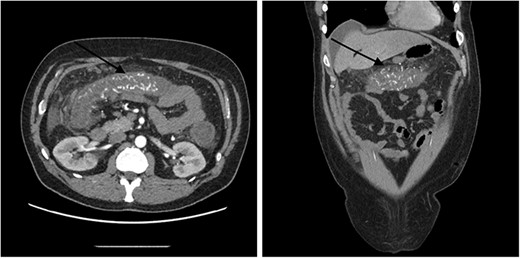

A 51-year-old male patient presented to the emergency department with 24 hours of severe abdominal pain and rectal bleeding, as well as 4 months history of non-mucous diarrhoea with stool frequency of up to 12 episodes per day. He had a background of poorly differentiated adenocarcinoma of the ascending colon (T3N0M0), which was treated with laparoscopic right hemicolectomy 1 year prior to this presentation. His follow-up colonoscopy 6 months prior to admission demonstrated evidence of diverticular disease and colitis although biopsies were normal. On admission, the patient was haemodynamically stable and physical examination did not reveal signs of peritonism. Laboratory studies demonstrated a haemoglobin drop of 4 g/dl (15.9–10.8 g/dl) but no evidence of abnormal coagulation. Stool samples were negative for infectious causes. The diagnosis of ischaemic colitis was made by contrast-enhanced computed tomography (CT) scan with CT angiography, which revealed AVMs in the territory of SMA and IMA and acute massive congestive ischaemic colitis affecting remaining colon and rectum (Figs 1 and 2).

Contrast-enhanced abdominal CT images of inferior mesenteric AVM causing acute congestive ischaemic colitis affecting descending and sigmoid colon, and rectum.